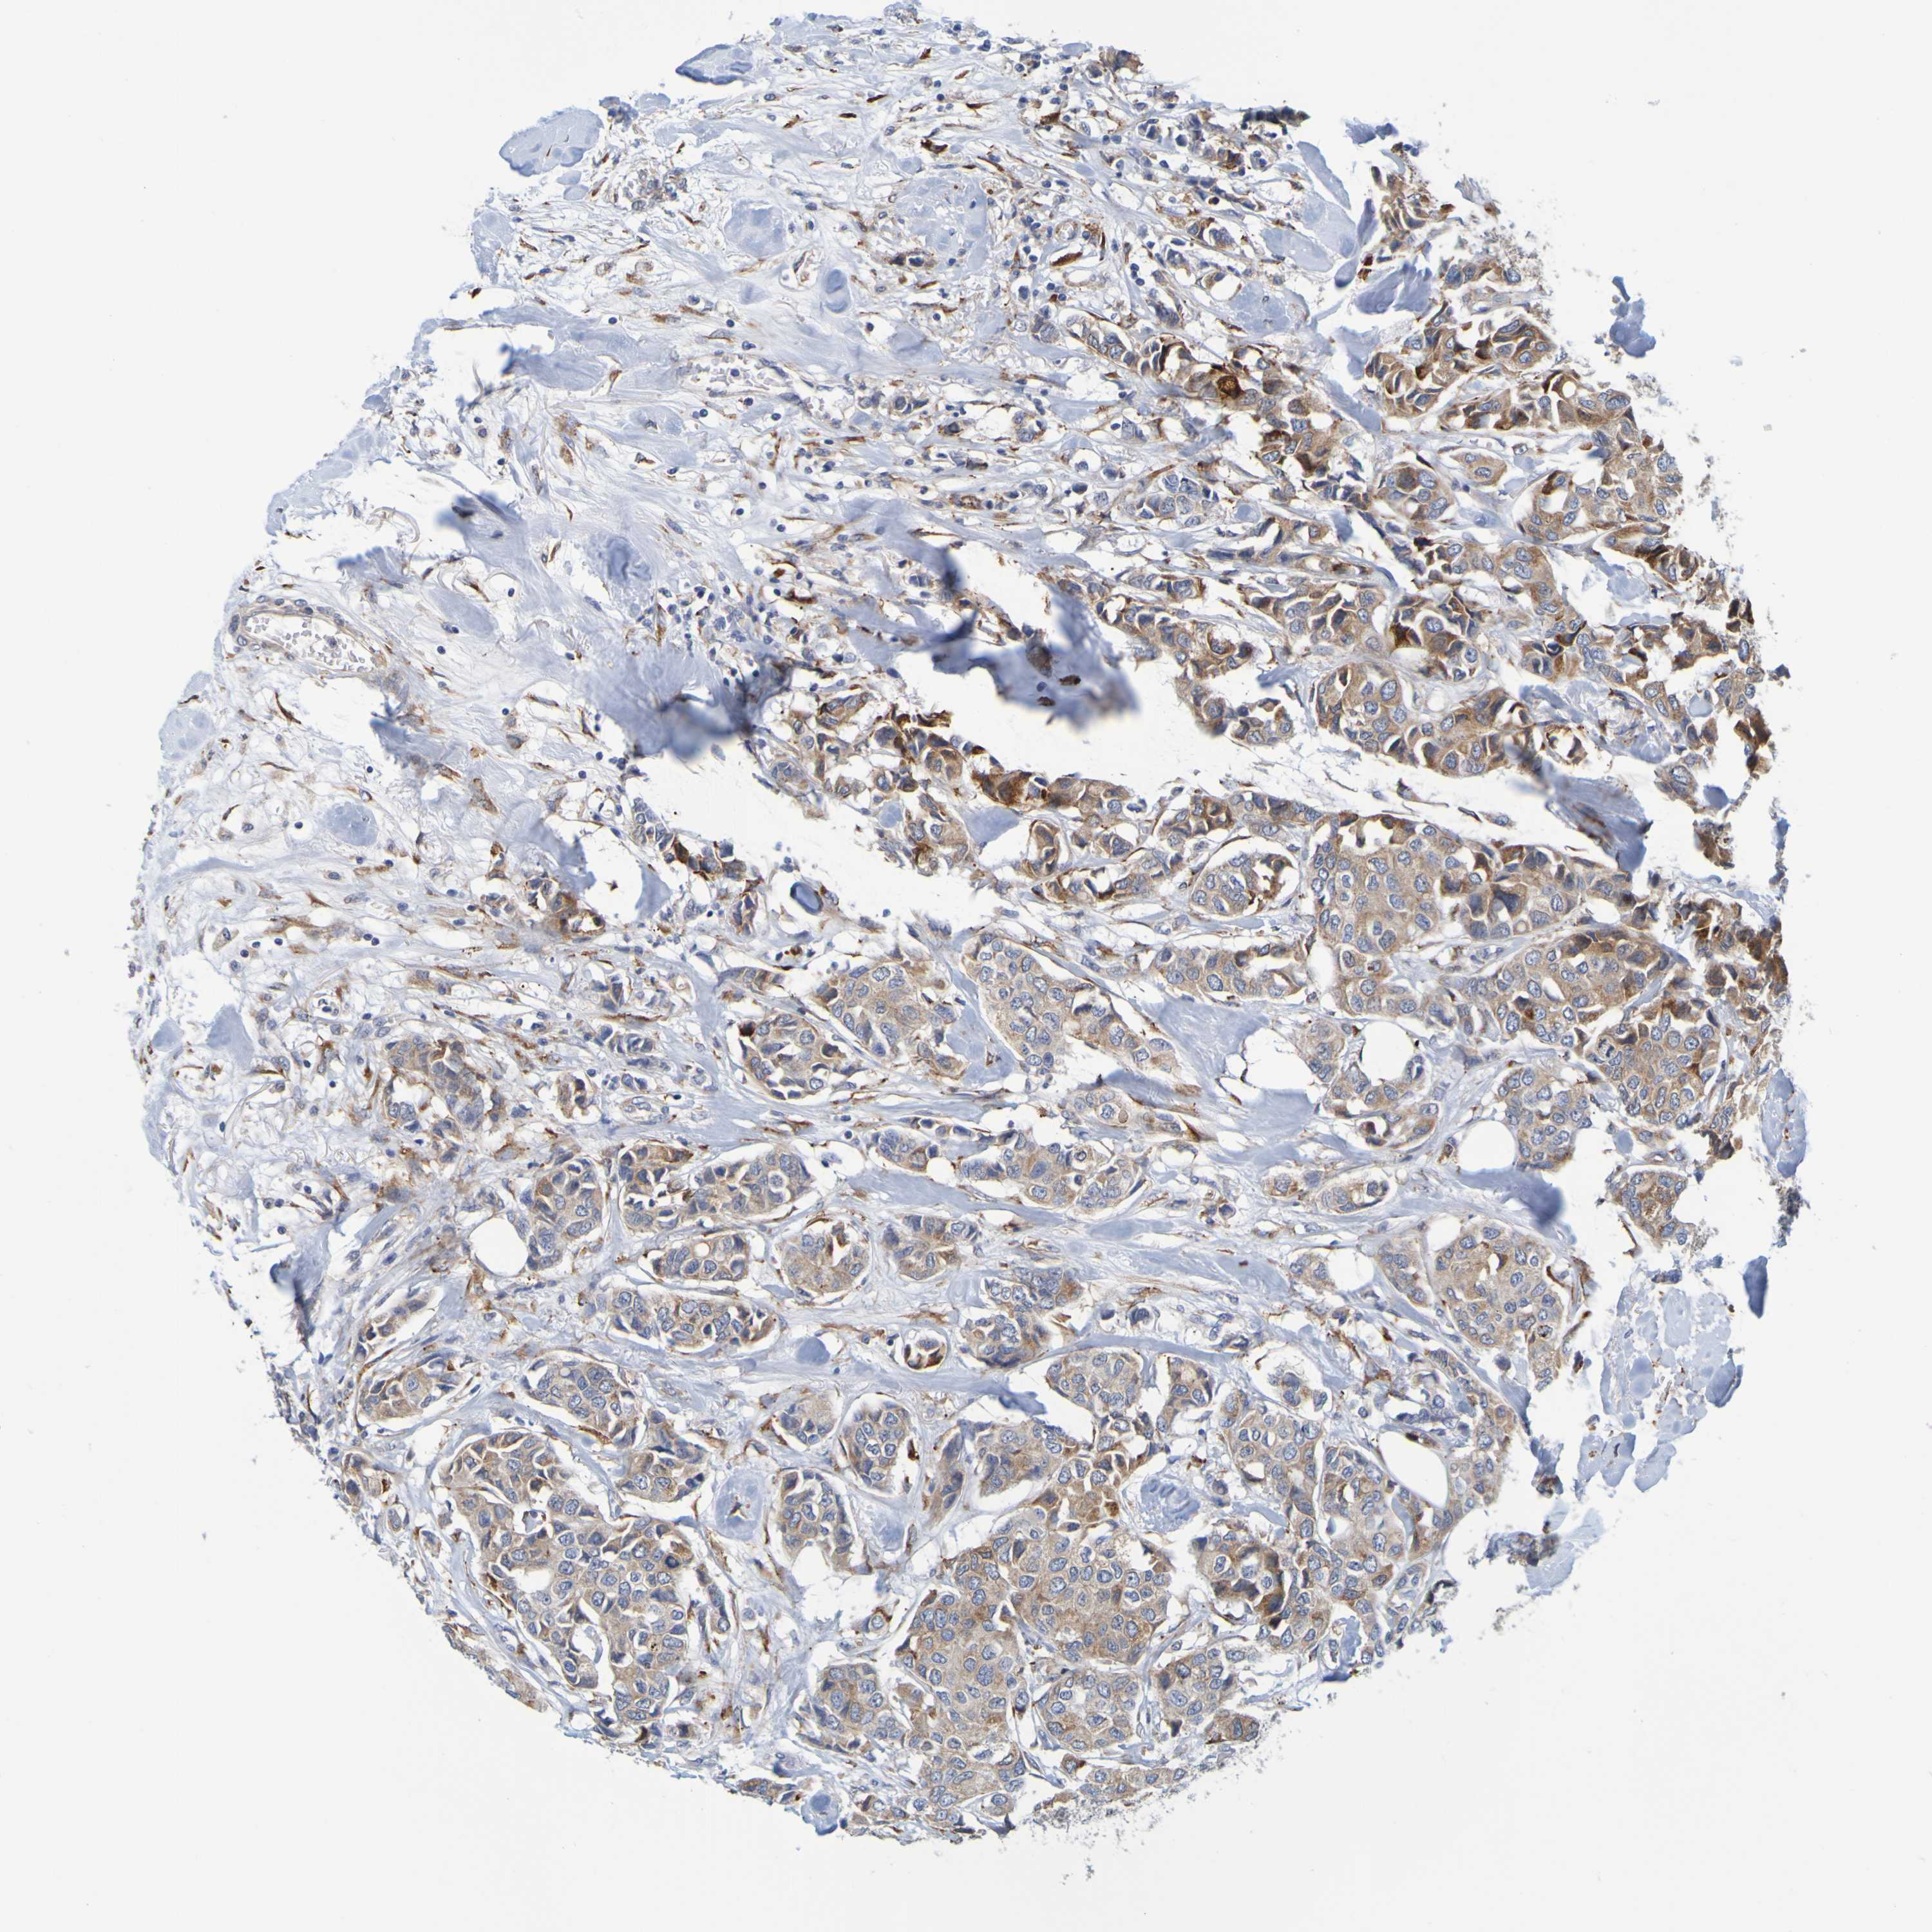

CANCER BREAST CANCER Show tissue menu

BRCA TCGA BRCA VALIDATION PROTEIN EXPRESSION